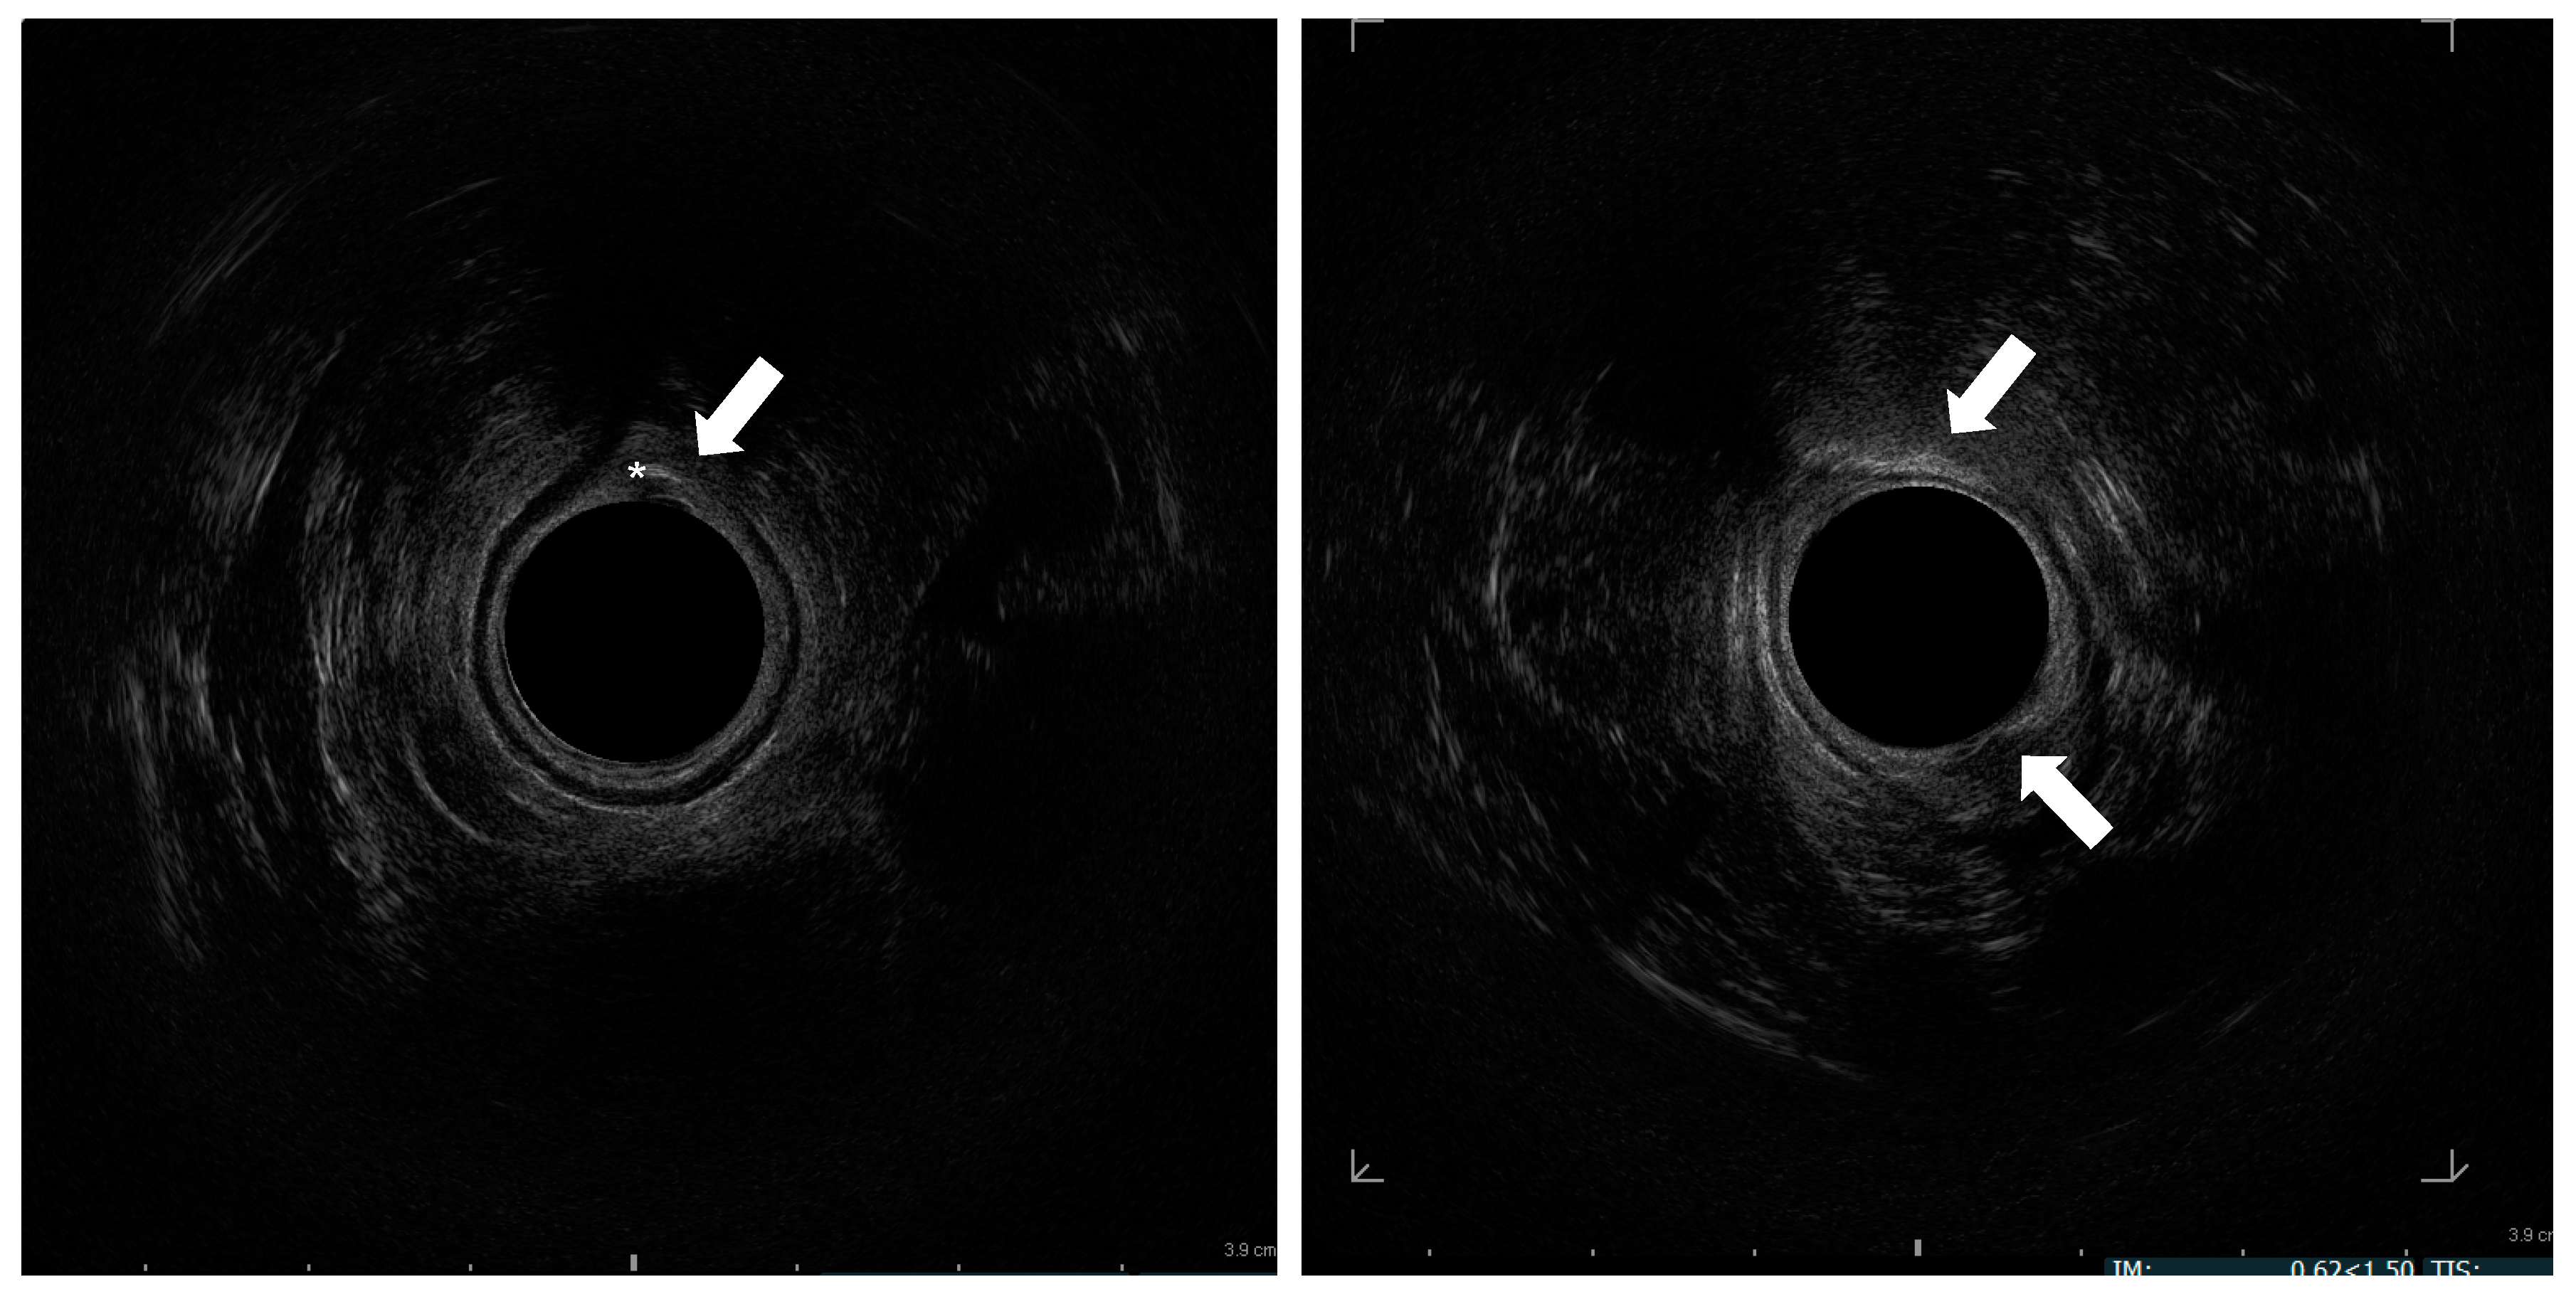

Figure 2.

Endosonographic axial sections of the middle anal canal. Asterisk: needle in the internal anal sphincter; Arrow: injected fat tissue h 6 and 12.